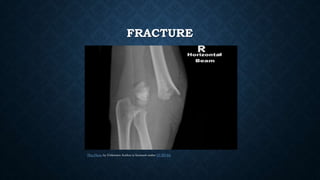

FRACTURE

This Photo by Unknown Author is licensed under CC BY-SA

FRACTURE This Photo byUnknown Author is licensed under CC BY-SA